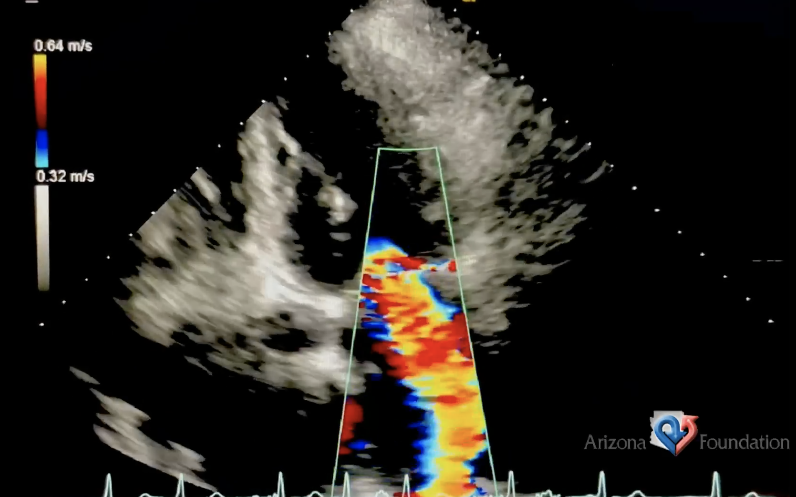

What Doppler findings are expected from this exam?

Increased systolic flow reversal on the pulmonary vein tracing

Note the width and length of the jet

Severe TR